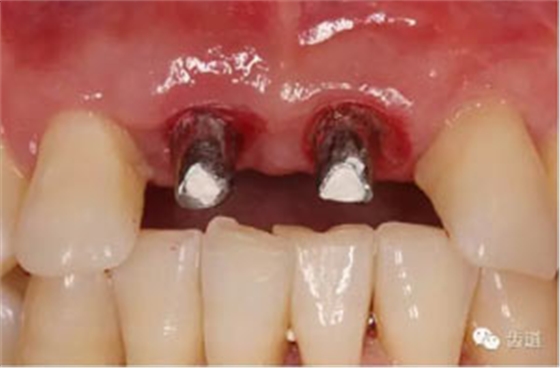

患者對(duì)美觀要求較高,與患者溝通后,擬定采用骨環(huán)技術(shù),同期種植并增加骨寬度和高度。

患者不愿才用自體骨移植,遂建議采用同種異體骨骨塊(皮質(zhì)骨)進(jìn)行骨環(huán)手術(shù)。 種植手術(shù):

修復(fù)治療: